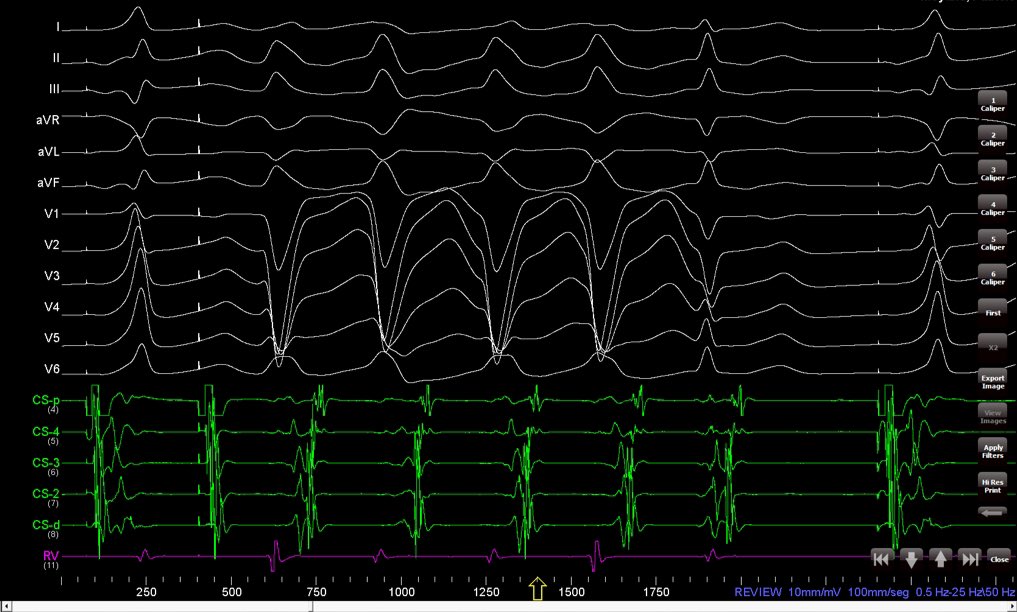

His-refractory PVC delivered from LV. RV dissociation in ORT using a left posterior AP. RV TCL remained unchanged. Case from today at Hospital Posadas This is the forth patient included and we can reproduce this phenomenon in all cases.

His-refractory PVC delivered from LV.

RV dissociation in  ORT using a left posterior AP. RV TCL remained unchanged.

Case from today at <a href="/hospitalposadas/">Hospital Posadas</a>

This is the forth patient included and we can reproduce this phenomenon in all cases.